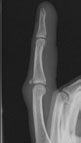

Central-Slip-Avulsion-Imaging

A central slip injury can be due to either a fracture at the base of the middle bone (avulsion) or from a tear in the fibres of the central slip itself (tendinous). You may need an x-ray to check if the bone is broken as well as the tendon being damaged. Your Hand Therapist, Physiotherapist or Occupational Therapist can organise an Xray referral for you. They will also assess your finger movement, swelling and pain in order to confirm the diagnosis.